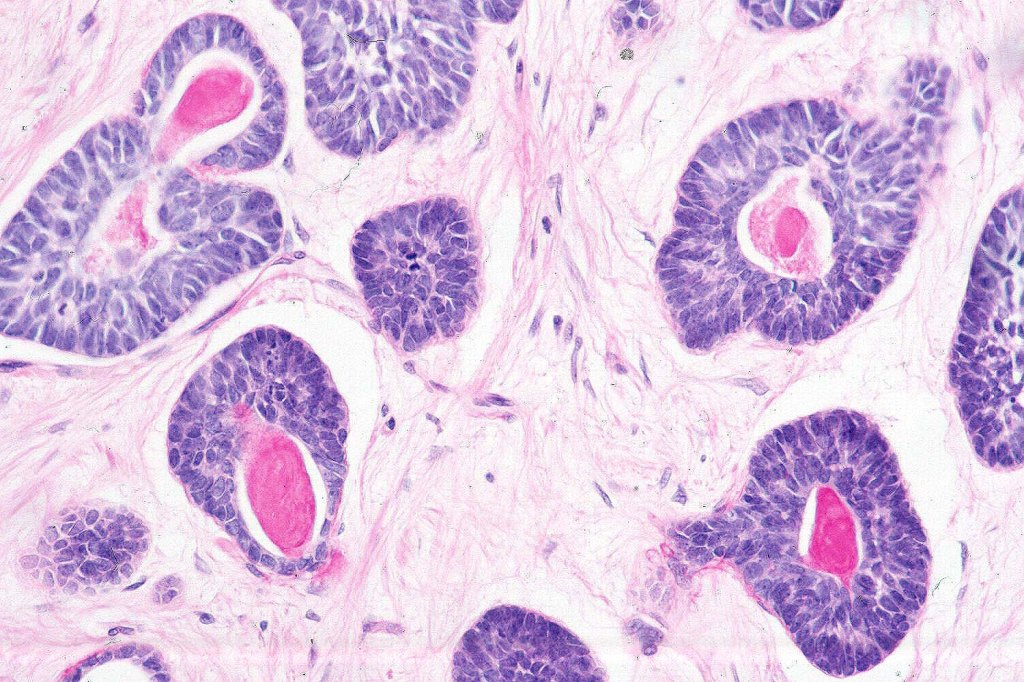

Histological features

•Biphasic tumor (myoepithelial & epithelial)

•Cribriform nests, tubules , cords & solid nodules

•Small ducts and pseudocysts